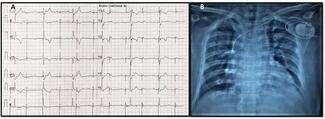

A 59-year-old Asian woman with paroxysmal supraventricular tachycardia (PSVT), diabetes, and dyslipidemia was hospitalized with palpitations and chest discomfort. Her electrocardiogram showed short RP tachycardia with a heart rate of 167...